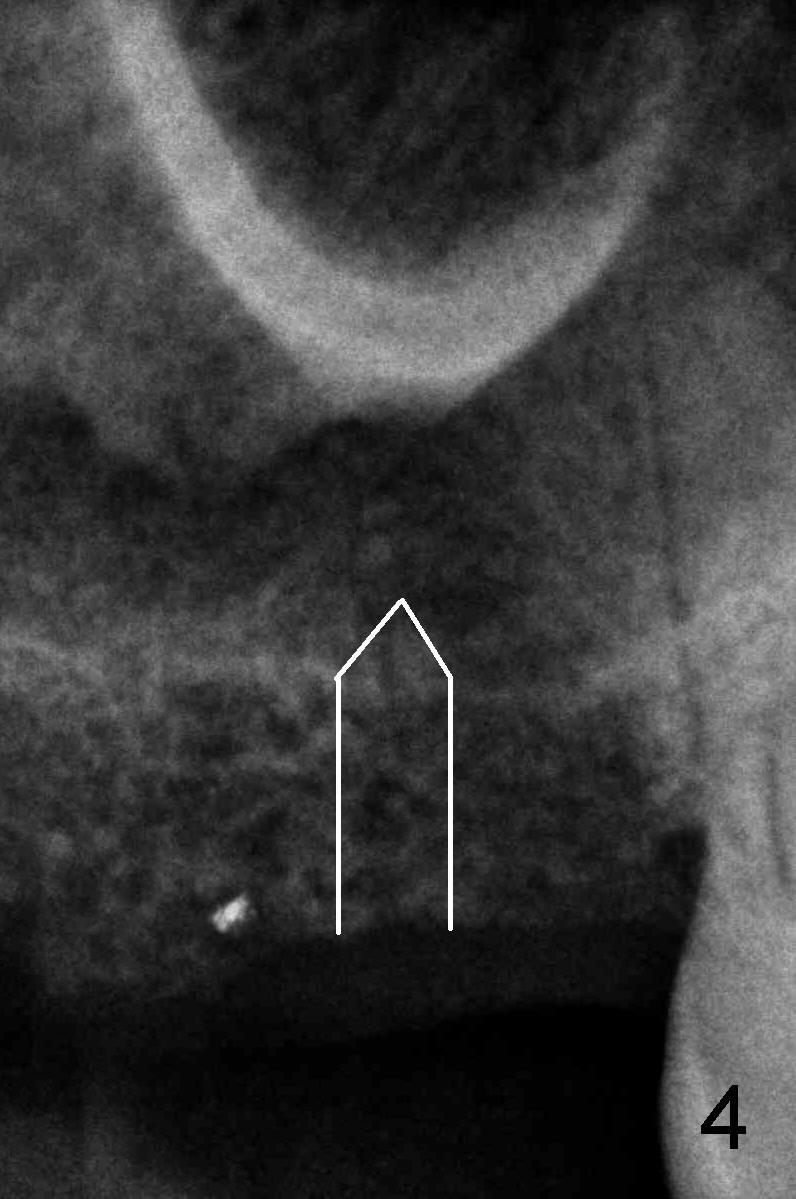

Anyway, a 1.6 mm pilot drill or 2 mm osteotome may be used to initiate osteotomy at the depth of 4-5 mm (Fig.3).  An explorer is used to check whether the sinus membrane has been reached or not.  As the diameter of bone expanders or osteotomes increases, the depth of the osteotomy increases (Fig.4), pushing the native bone into the sinus.  Each step check sinus membrane integrity by using an explorer or doing nose blowing test.  The implant can also push more bone upward when it is being placed (Fig.5).  Combined lateral and crestal sinus lift is not recommended in this case because of limited access.